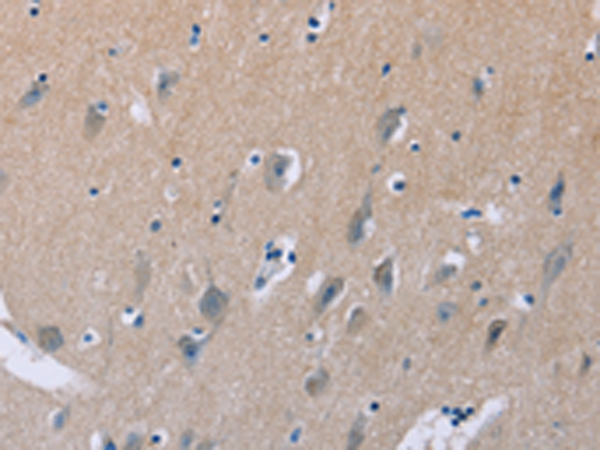

分类: 科研抗体货号: P11000别名: MDS, LIS1, LIS2, MDCR, PAFAH应用: IHC反应种属: Human, Mouse, Rat